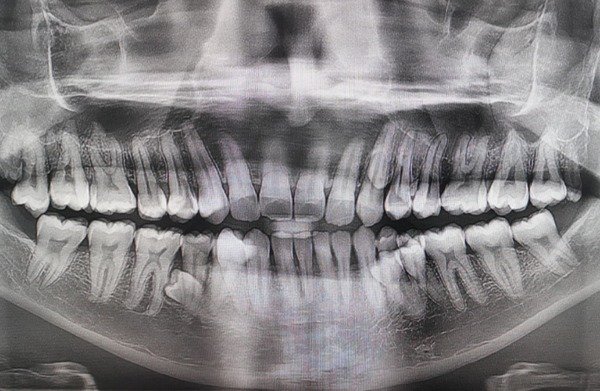

A Malaysian man was found to have 42 teeth—ten more than the average person